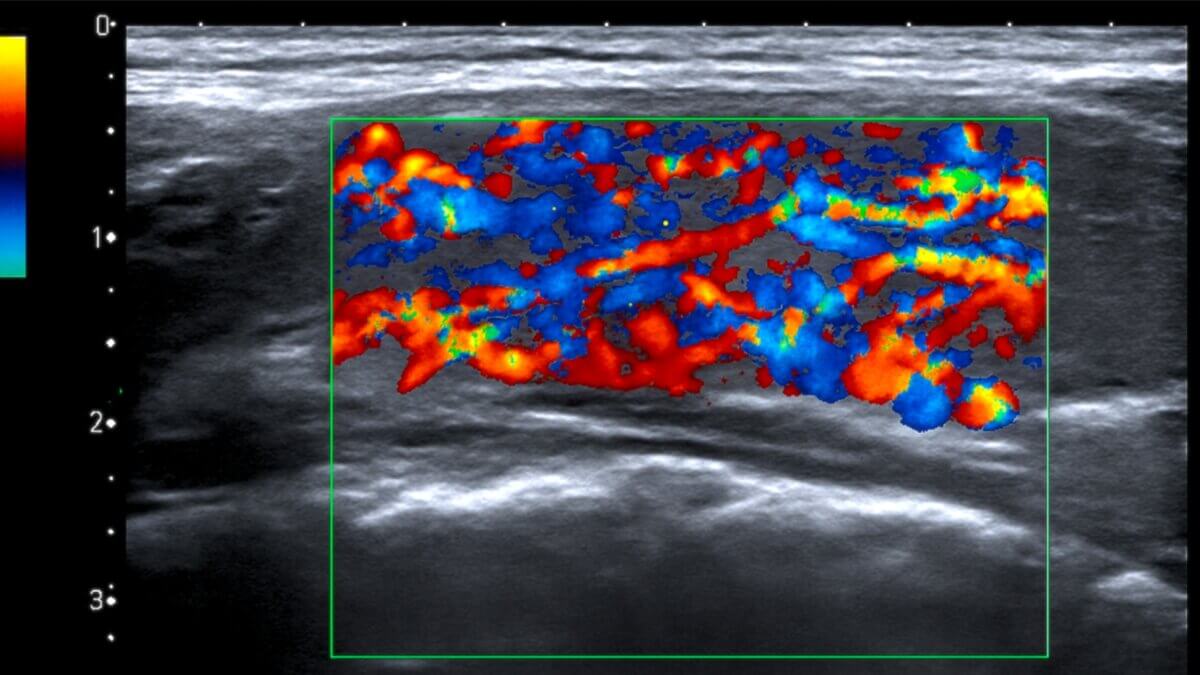

Vaskuläres Inferno

Englisch: thyroid inferno

Das vaskuläre Inferno bezeichnet ein sonographisches Zeichen bei der Ultraschalluntersuchung der Schilddrüse. Durch eine stark erhöhte Durchblutung des Schilddrüsenparenchyms kommt es zu einem unübersichtlichen Gesamtbild mit dynamischen Strömungsmustern.